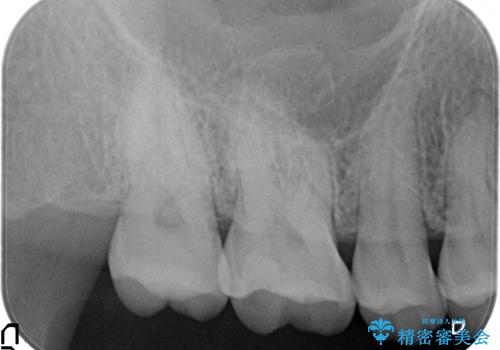

- 古い銀歯をセラミックで治療したいといらっしゃった方の症例です。

銀歯及び虫歯を除去後、セラミックインレーによる修復を行いました。